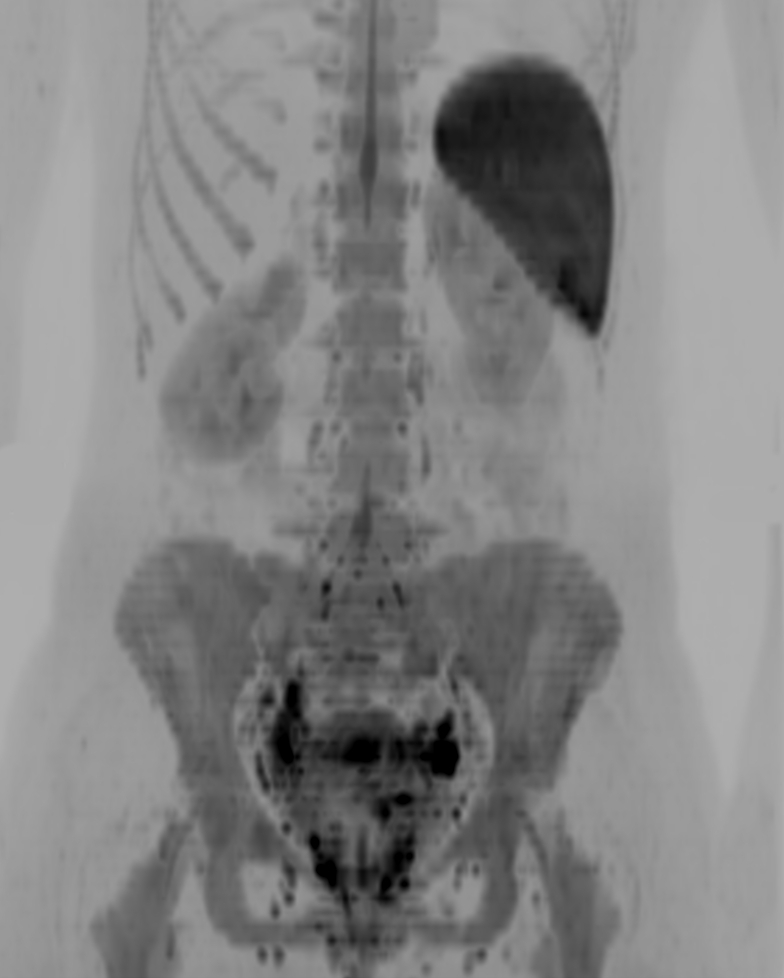

Coronal DWIBS